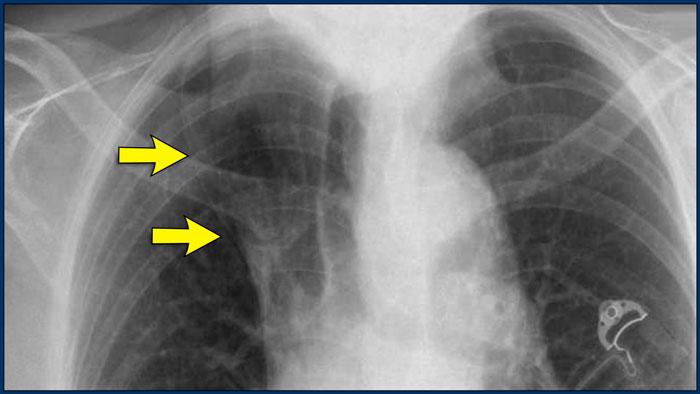

Thùy tĩnh mạch đơn

Một biến thể bình thường thường gặp, thùy tĩnh mạch đơn, được hình thành khi tĩnh mạch đơn đi theo một đường bất thường về phía bên, tạo ra một rãnh màng phổi sâu ở thùy trên phổi phải.

Trên phim X-quang, hình ảnh này biểu hiện là một đường cong mảnh đi ngang qua vùng phổi trên phải, thường kết thúc bằng một đám mờ hình giọt nước (tĩnh mạch đơn) trong rãnh tĩnh mạch đơn.

Đây là một bệnh nhân khác có thùy tĩnh mạch đơn.

Tĩnh mạch đơn được thấy như một cấu trúc dày trong rãnh tĩnh mạch đơn.